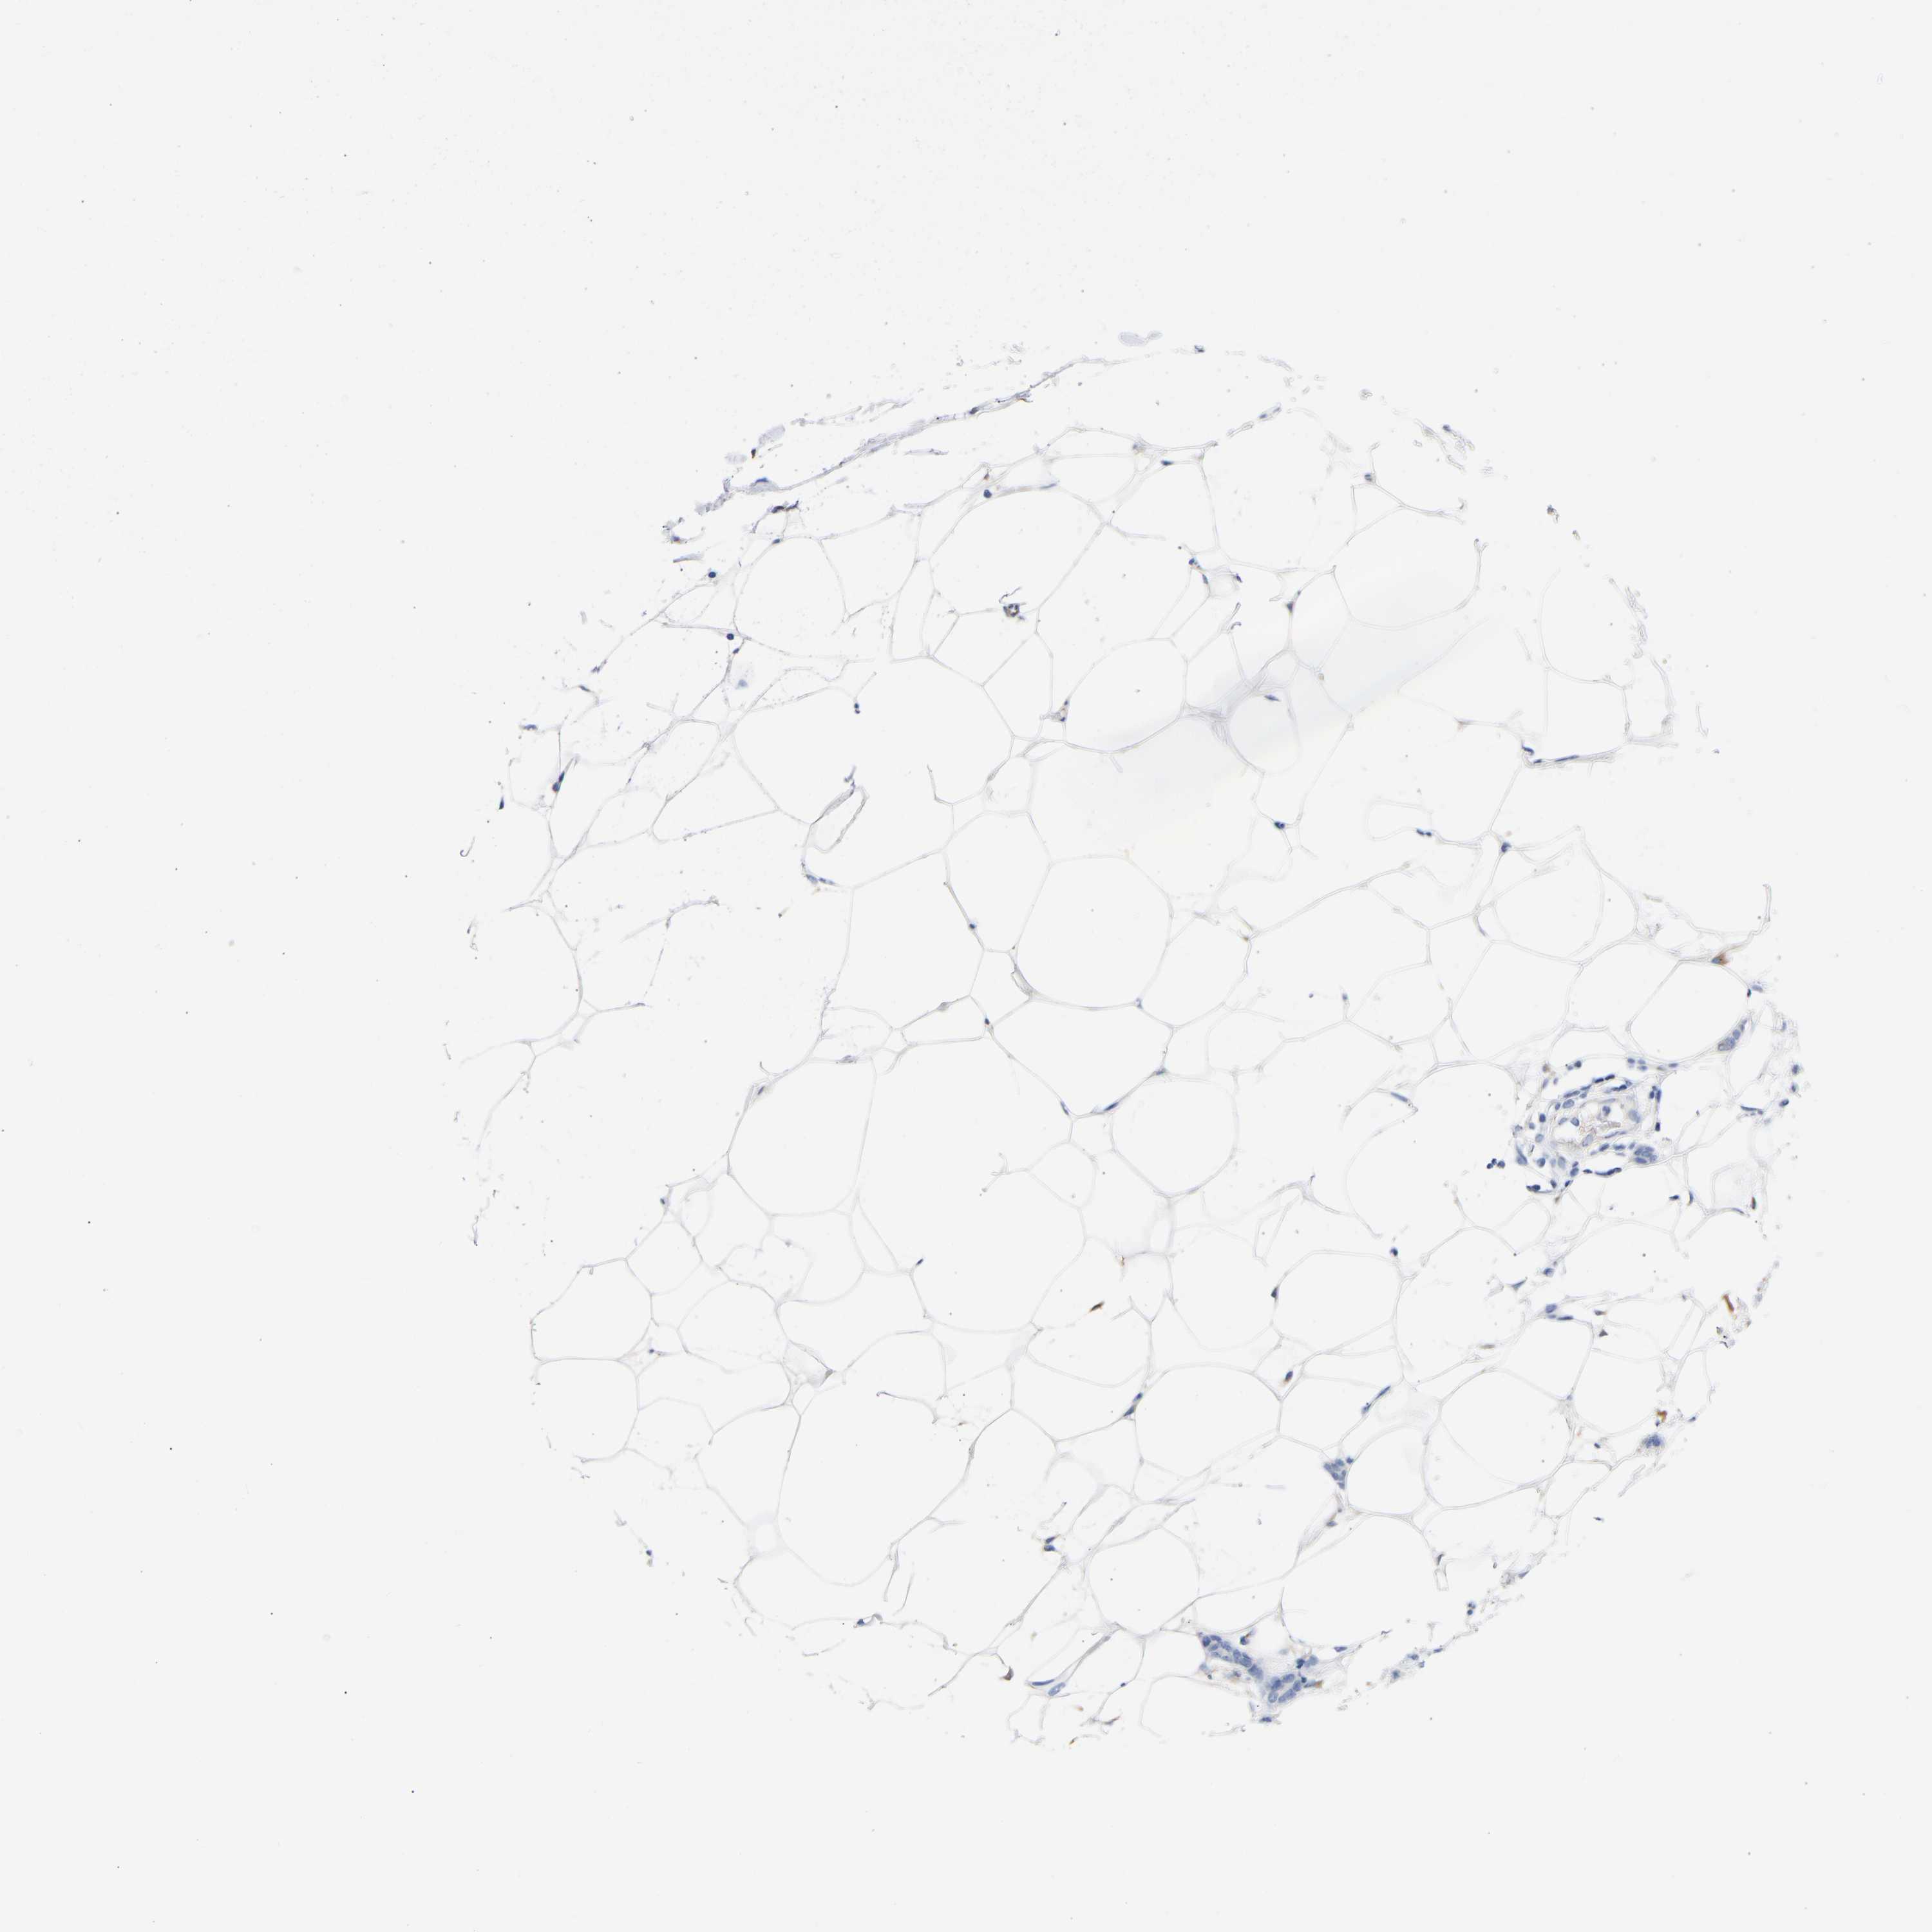

CANCER BREAST CANCER Show tissue menu

BRCA TCGA BRCA VALIDATION PROTEIN EXPRESSION

Breast cancer

Human cancer